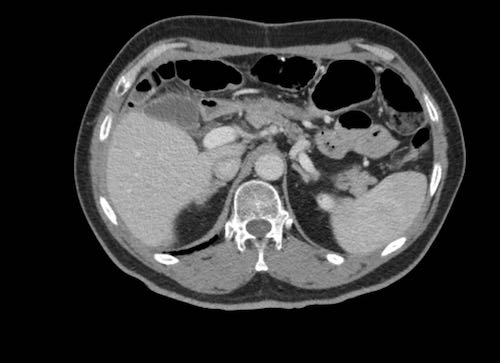

Cuộn xem ảnh CT

Ca lâm sàng 1

Cuộn qua các lát cắt.

Bạn có thể phát hiện tất cả các tổn thương cấy ghép phúc mạc không?

Bệnh nhân này đã được phẫu thuật và toàn bộ phúc mạc được ghi nhận phủ kín bởi các tổn thương u dạng kê.